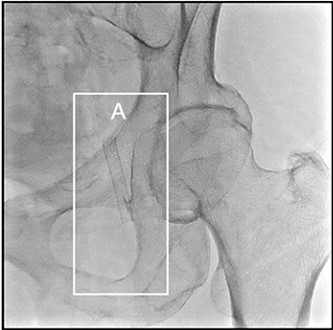

Режим Dynamic trace

Dynamic trace – режим дослідження кінцівок, передбачає рух деки столу за напрямком поширення контрастної речовини по периферичних судинах в режимі рентгенографії.